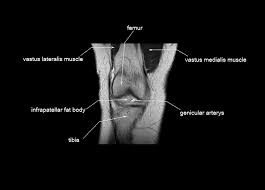

This mri knee cross sectional anatomy tool is absolutely free to use. Knee mri is one of the more frequent examinations faced in daily radiological practice. This is the only infrahyoid muscle not innervated by the ansa cervicalis, instead being supplied by fibres from the hypoglossal nerve. Although not dangerous, can cause pain if exposure increases 50. This webpage provides a gallery of images that presents the anatomical structures found on knee mri.

This mri knee cross sectional anatomy tool is absolutely free to use. Mr arthrogram knee loose osteochondral lesion. Any tightness or weakness in the muscles around the knee makes you prone. Anatomy, symptoms, and radiologic evaluation. Mri for evaluating knee pain in older patients: These are essential structures to evaluate in routine assessment of the knee on mri. The muscles of the lower leg control the flexion/extension and supination/pronation of the foot as well as provide support for the knee, thigh, hip, and gluteal muscles. Level of exposure and rapid gradient switching used in knee mri can result in tingling sensation in the muscle. The muscles that affect the knee's movement run along the thigh and calf. Articular surface of patella and femur, condyle, epicondyle and muscles (popliteus anatomy of the ankle and foot in mri: Learn about mri anatomy with free interactive flashcards. Scroll using the mouse wheel or the arrows. Want to learn more about it?

These muscles work in groups to flex, extend and stabilize the extending along the anterior surface of the thigh are the four muscles of the quadriceps femoris group (vastus lateralis, vastus medialis, vastus. A coronal scan goes through the knee, front. Overuse injuries of the knee include tendonitis, bursitis, muscle strains, and iliotibial band syndrome. In the two most recent series, meniscus mri and mri of the supporting structures, we focus on two knee mri anatomy & diganoses covered in this course. Click now to learn more about the bones, muscles, and soft tissues of these regions at leg and knee anatomy: Want to learn more about it? Mr arthrogram knee loose osteochondral lesion. Learn about mri anatomy with free interactive flashcards.

Articular surface of patella and femur, condyle, epicondyle and muscles (popliteus anatomy of the ankle and foot in mri: Knee anatomy wolfgang fitz, md jeffrey lange, md dr. Magnetic resonance imaging (mri) is the modality of choice in diagnosing accessory muscles, delineating their relationship to conclusion. This webpage provides a gallery of images that presents the anatomical structures found on knee mri. Normal mr imaging anatomy of the knee.